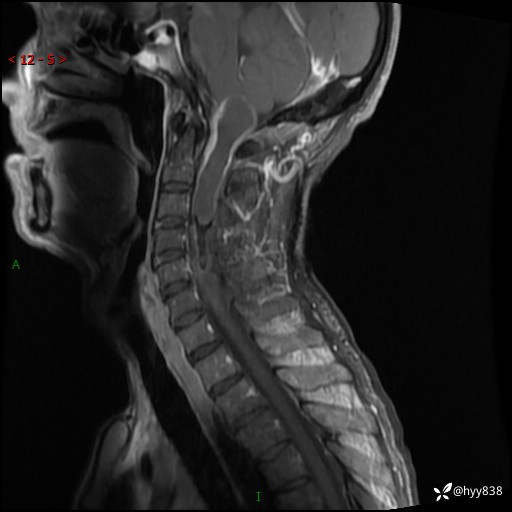

颈椎MRI平扫(sag T1WI+T2WI-fs+axi T2WI)

简要病史:患者约于2年前无明显诱因出现右手麻木伴有精细活动差,无行走不稳,家属将患者送至当地县人民医院行颈椎MR提示:颈髓占位性病变。患者未系统治疗治疗。后病情逐渐加重,4个月前出现四肢无力,右侧为甚,行走不稳,伴有四肢感觉减退,伴有大便偶有失禁,现患者及家属为求进一步治疗入我院,遂以“椎管占位”收住我科。 发病以来,患者精神饮食睡眠好,大小便正常,体力体重未见明显改变。

辅助检查:MRI

临床诊断:椎管占位